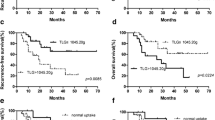

Clinicopathological factors and metabolic parameters were included in survival analysis. In univariate analysis, age (P = 0.017), INSS (P = 0.002), COG (P = 0.003), Chromosome 11q (P = 0.007), NSE (P < 0.001), SF (P = 0.003), LDH (P = 0.008), PSUVmax (P = 0.011), PSUVpeak (P = 0.035), PMTV (P = 0.025), IMH (P < 0.001), WSUVmax (P = 0.002), WSUVpeak (P = 0.006), WMTV (P < 0.001), WTLG (P = 0.001), and WMH (P < 0.001) were significantly associated with PFS. Variables with significant differences in the univariate analysis were included in multivariate analysis. Multivariate analysis identified that INSS (P = 0.011), WMTV (P < 0.001), WTLG (P = 0.004) and WMH (P < 0.001) were independent risk factors for PFS (Table 4).

In univariate analysis of OS, MYCN (P = 0.025), NSE (P < 0.001), SF (P = 0.006), LDH (P < 0.001), PSUVmax (P = 0.001), PSUVpeak (P = 0.003), IMH (P = 0.003), WSUVmax (P < 0.001), WSUVpeak (P = 0.001), WMTV (P = 0.003), WTLG (P = 0.012), and WMH (P < 0.001) were significant associated with OS. However, in multivariate analysis, only NSE (P = 0.002) and WMH (P < 0.001) remained significant. Therefore, NSE and WMH were identified as independent prognostic risk factors for OS (Table 4).

Further evaluate tumor metabolic burden and WMH on survival

Based on the results of multivariate survival analysis, we further investigated the predictive effect of whole-body tumor metabolic burden and WHM. The optimal cut-off values for WMTV, WTLG and WMH were 413.14, 1044.14 and 0.448, respectively, determined by the area under the receiver operating characteristic curve. Significant differences were observed in WMTV and WTLG for PFS (P < 0.001, P < 0.001, respectively) and OS (P < 0.001, P < 0.001, respectively). Similarly, WMH also manifested significant differences for PFS (P < 0.001) and OS (P = 0.004) (Fig. 3). Two representative NB patients with high and low WMH values were presented in Fig. 4.